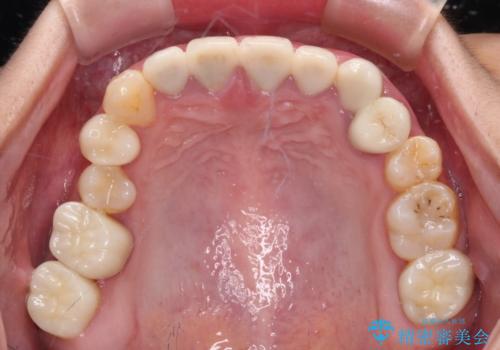

むし歯だらけの奥歯 セラミッククラウンによるむし歯治療

- 奥歯のむし歯を気にして来院された患者様です。

根管治療や歯周外科処置後にフルジルコニアクラウンにて補綴治療することとしました。